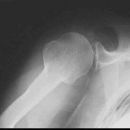

Schulter seitlich (Y-View)

Patient steht mit dem Bauch am Stativ (p.a.), gesunde Seite um 45° anheben, kranke Seite liegt auf, Arm der aufzunehmenden Seite im Ellenbogen um 90° gebeugt.

Senkrecht in Gelenkspalt bei Format 18/24.

Bei Format 24/30 oberer Kassettenrand: 2 Querfinger oberhalb der Schulter, prox. Humerus mit in der Einblendung.

Scapula stellt sich Y-förmig ohne Rippenüberlagerung dar. Humerus und Scapula überdecken sich. Gelenkpfanne befindet sich im Schnittpunkt der 3 Schenkel vom Y.